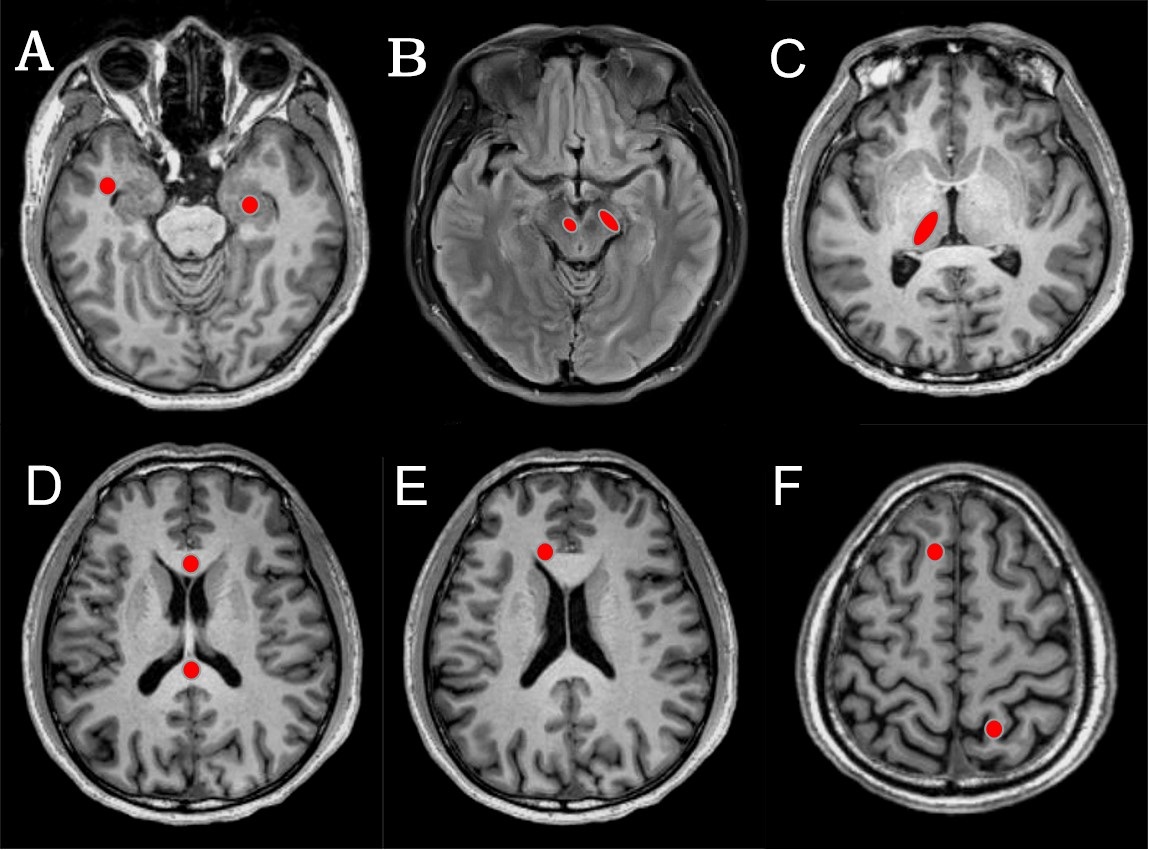

Fig. 1. Placement of ROI. Red areas represent ROIs of temporal lobe (A, right), hippocampus (A, left), red nucleus (B, right) and substantia nigra (B, left), thalamus (C), corpus callosum knee (D, upper) and corpus callosum pressure (D, lower), cingulate gyrus (E), frontal lobe (F, right), and parietal lobe (F, left).